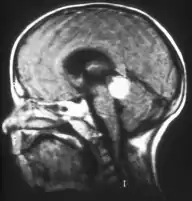

El retinoblastoma tiende a extenderse hacia el cerebro y la médula ósea, y más raramente se disemina por los pulmones. Estos son factores de pronóstico adverso, así como la invasión coroidal y a través del nervio óptico.[1]